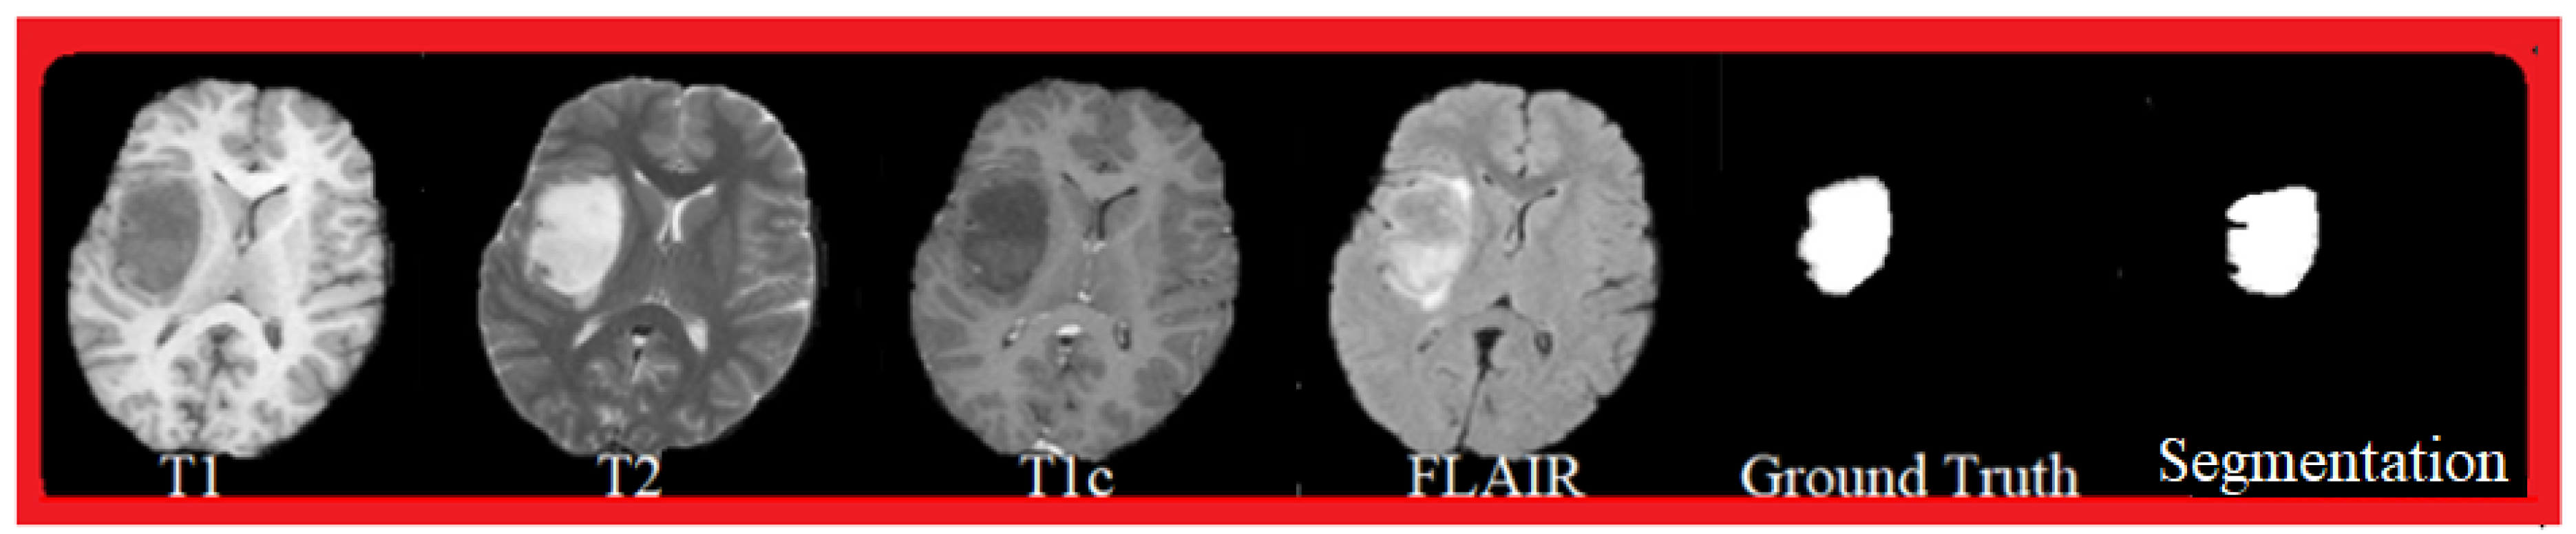

4.2. Experiments on the BraTS 2015 Database

4.2.1. Database Description

4.2.2. Experiments